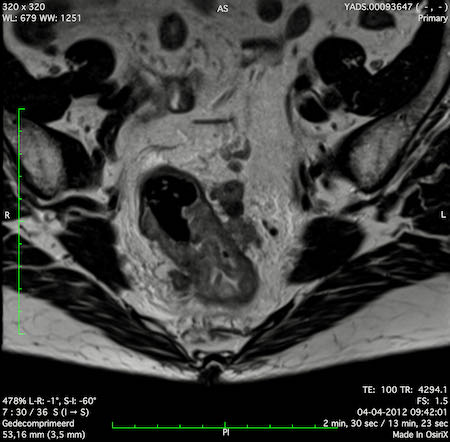

Hình ảnh

Các hình ảnh được cung cấp cho thấy ung thư biểu mô tế bào nhẫn với tình trạng dày lan tỏa thành trực tràng, hình ảnh bia bắn điển hình, và sự xâm lấn mỡ mạc treo trực tràng.